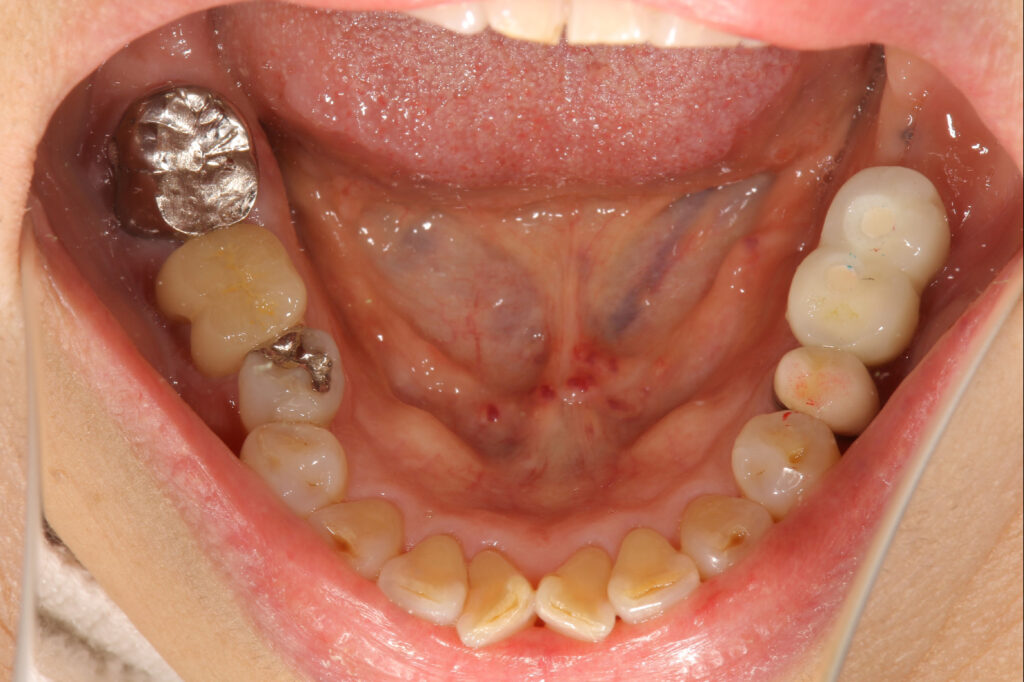

左下奥歯を2本インプラント治療した症例

| 主訴 | 前歯欠けた。その他虫歯治療してほしい。 |

| 年齢 | 70代女性 |

| 治療内容 | 根尖病巣で排膿もあり残すことが難しいため抜歯しインプラント治療へ。 歯槽骨の量が不足している場合に、人工骨や自家骨を移植し、特殊な膜で覆うことで骨の再生を促し、インプラントを埋入できるようにするGBRという治療法も併用。 最終的なかぶせものはご自身の歯と変わらないような仕上がりとなっています。 |

| 抜歯部位 | 左下6 |